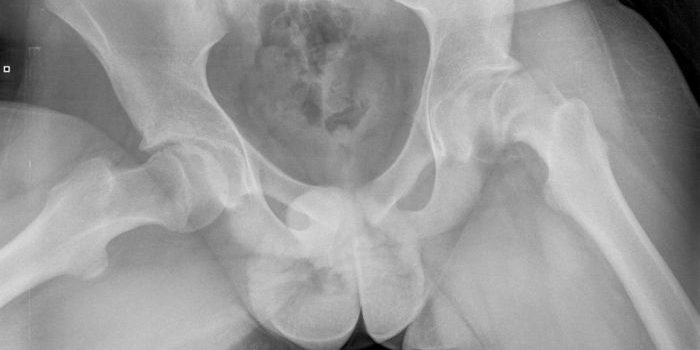

Operativni tim Klinike za ortopediju i traumatologiju UKC Tuzla izveo je operativni zahvat proximalnog dijela lijeve nadkoljenice, zbog epifiziolize ili poskliza proximalne epifize nadkoljenice kod 14-godišnjeg dječaka. Kako je istakao operator, prim. dr. Nedim Smajić, šef Odjeljenja dječije ortopedije, stanje zbog kojeg je pacijent operisan je rijetko i javlja se u procentu 10:100 000 adolescenata dobi od 10 do 17 godina, češće kod dječaka, adipozogenitalne konsitucije i povećane tjelesne težine. “U pitanju je poremećaj epifize koji dovodi do klizanja metafize prema naprijed i gore, u odnosu na epifizu koja ostaje u acetabulumu. Nastaje zbog djelovanja mehaničkih sila na promjenjenu zonu rasta, a čija je struktura već prije narušena, najčešće zbog hormonalnog disbalansa. Stanje se manifestuje bolom, ograničenom pokretljivošću i skraćenjem extremiteta”, pojašnjava prim. dr. Smajić i dodaje da je izbor terapije za epifiziolizu operacija bedrene kosti.

Prim. dr. Smajić je istakao da je uobičajno da se nakon manuelnog povlačenja pri pokušaju vraćanja epifize na njeno mjesto učini stabilizacija sa jednim vijkom što nosi rizik od oštećenja epifize u vidu nekroze i hondrolize zbog oštećenja krvnih sudova koji ishranjuju epifizu. “Operacija je podrazumjevala osteotomiju ili presjecanje kosti u trohanternoj regiji pod određenim uglovima i u dvije ravni, a u cilju vraćanja epifize na poziciju prije smicanja, bez manipulacija koje ugrožavaju vaskularizaciju i moguće oštećenje epifize”, kazao je dr. Smajić i pojasnio da su ovakvim pristupom opisane komplikacije svedene na minimum.